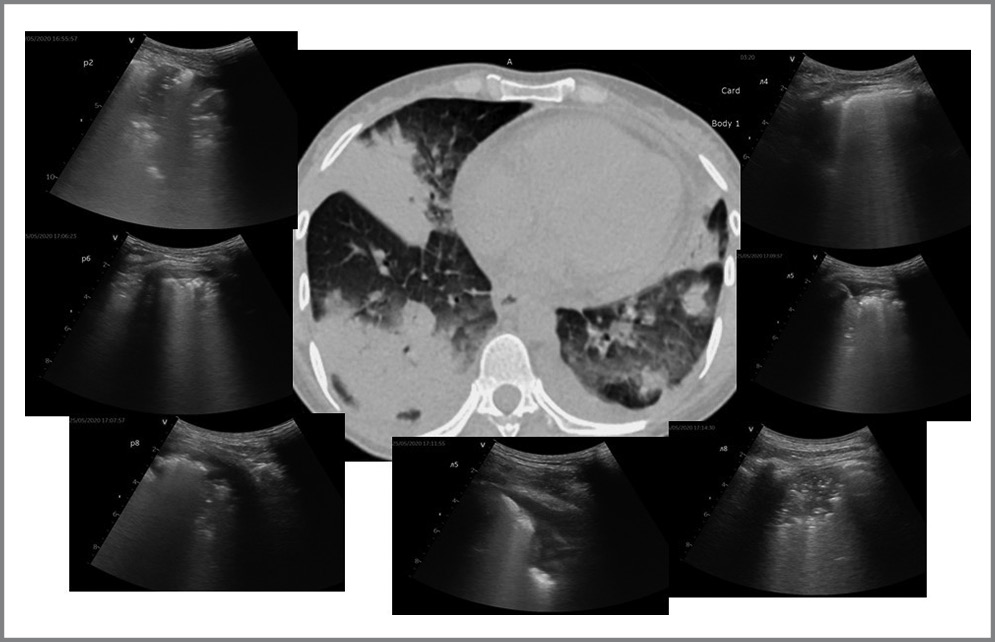

С целью выявления изменений легочной ткани, характерных для новой коронавирусной инфекции, применялся специальный протокол, который разработан нами таким образом, чтобы полученные данные посегментно сопоставлялись с результатами КТ легких. Таким образом, на основе разработанного протокола проводилась оценка 16 зон легких: для правого легкого зона RI на УЗИ соответствовала зоне СIII на КТ, RII–СV, RIII–СII,III, RIV–СIV, RV–СII,VI, RVI–СVIII,IX, RVII–СVI, RVIII–СX, а для левого легкого – зона LI–СIII, LII–СIV,V, LIII–СIII,IV, LIV–СV, LV–СII,VI, LVI– СVIII,IX, LVII–СVI, LVIII–СX (рис. 1).

Рис. 1. Пример протокола УЗИ легких с оценкой тяжести поражения. / Fig. 1. An example of a lung ultrasound protocol with an assessment of the severity of the lesion.

По данным УЗИ легких: УЗ-признаки двустороннего инфильтративного поражения легких, выраженного преимущественно в виде крупных транслобарных консолидаций в нижних сегментах обоих легких. В верхних отделах обоих легких отмечаются минимальные изменения (рис. 5).

Рис. 5. Сопоставление УЗИ легких с данными КТ согласно разработанному протоколу у пациента с COVID-19 при поступлении в стационар. / Fig. 5. Comparison of lung ultrasound with CT data according to the developed protocol in a patient with COVID-19 upon admission to the hospital.

На КТ органов грудной клетки: двусторонние инфильтративные изменения легких (высокая вероятность COVID-19-пневмонии, нельзя исключить двустороннюю пневмонию смешанного генеза), тяжелая степень поражения легких (КТ-3). Процент поражения легких составляет 60–70%.